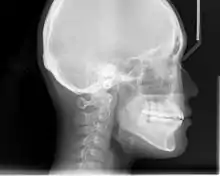

An X-ray taken for skull analysis

In the postwar period, cephalometric radiography[11] started to be utilised by orthodontists for measuring changes in tooth and jaw position caused by growth and treatment.[12] The x-rays showed that many Class II and III malocclusions were due to improper jaw relations as opposed to misaligned teeth. It became evident that orthodontic therapy could adjust mandibular development, leading to the formation of functional jaw orthopedics in Europe and extraoral force measures in the US. These days, both functional appliances and extraoral devices are applied around the globe with an aim of amending growth patterns and forms. Consequently, pursuing true or at least improved jaw relationships had become a main objective of treatment by mid-20th century.[5]